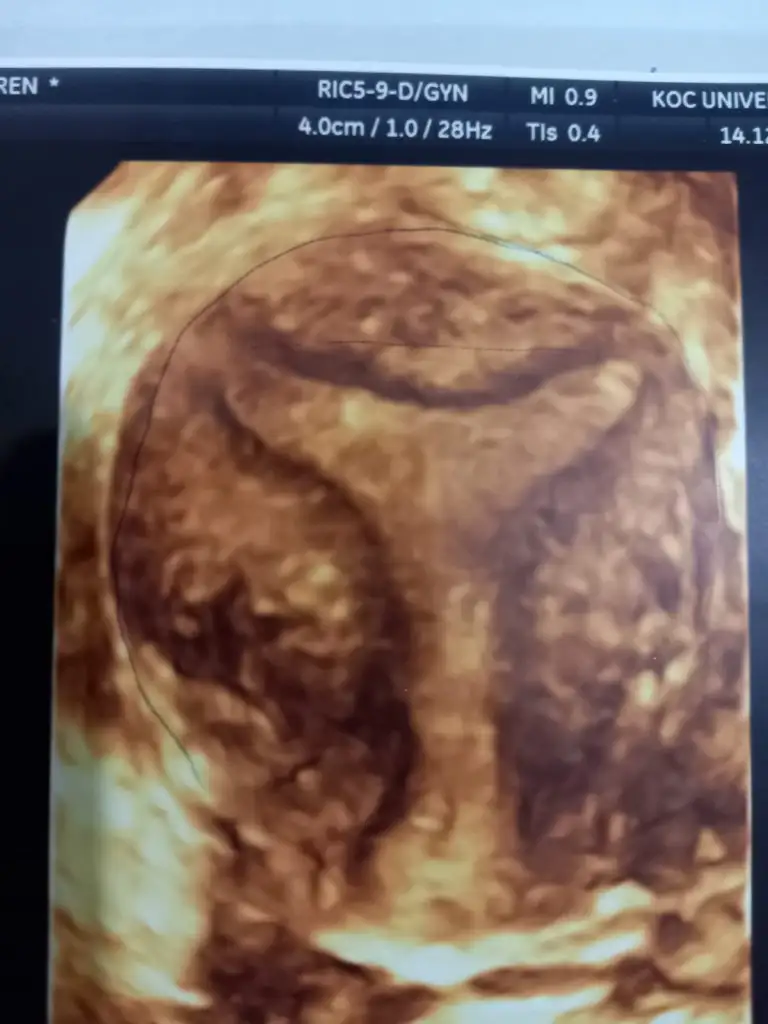

Benimkine benziyor biraz doktorların ortalama yarısı yaptırın derken yarısı gerek yok dedi. Gerek yok diyenlerin içinde dr yücel karaman da var .. kimyasal ve boş gebelik geçirdim ben de bu arada… yücel hocaya tekrar gideceğim ama doktorlar erken dönem düşüklerim t rahimle ilgisi yok diyor bilmiyorumİyi aksamlar herkese.benim de sorunum t şeklindeki rahmim. 1 yıl içinde bildiğim ve takip ettiğim kadarıyla 2 kimyasal gebelik 1 tane de bebek 8 haftalikken kürtaj gecirdim. Bu ay doktora gittim ve rahmimin t şeklinde olduğunu öğrendim.bikac ay daha dene eğer hamile kalamazsın deneyebiliriz operasyonu dedi. Eke ekledim görüntüyü sizce cok mu dar, olmali miyim ameliyat. Yardımcı olursanız sevinirim